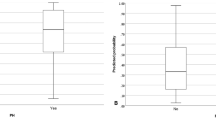

From a practical viewpoint, CT detection and quantification of ILD extent is essential, irrespective of the PH group. Indeed, mild parenchymal lung changes (i.e., fibrosis and/or emphysema) in patients with idiopathic PAH are associated with worse survival [40], probably identifying a distinct PH phenotype of idiopathic PAH closer to group II PH [41]. Moreover, among patients with SSc-related PH, those with extensive ILD (i.e., CT extent > 30%) are associated with worse survival than those with PAH and low DLCO but no or limited ILD [42, 43].

Nonspecific, subpleural peripheral bands or consolidation areas resembling parenchymal scars can frequently be encountered in CTEPH (Fig. 2d) [46], thus prompting careful evaluation of PAs (see further in the text).